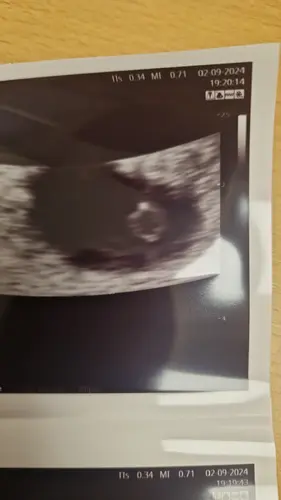

Vandaag met 5 weken en 2/3 dagen! We mochten een mooi kloppend hartje zien 😍😍💖

Vandaag met 5 weken en 2/3 dagen! We mochten een mooi kloppend hartje zien ...